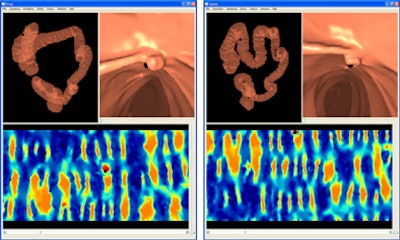

![]() |

| Endoluminal view of a polyp after using the proposed registration method to find the correspondence between the prone and supine colon surfaces, indicated by the black dot in both 3D renderings and 2D representations. |

A training dataset was used to find suitable parameters to constrain the cylindrical registration method. Those same registration parameters were then applied to a different set of 13 validation cases that comprised eight fully distended cases and five cases exhibiting multiple colonic collapses.

All polyps were found to be well aligned, with a mean registration error of 5.7 ± 3.4 mm. An additional 1,175 reference points on haustral folds spread over the entire endoluminal colon surface resulted in an error of 7.7 ± 7.4 mm. Overall, 82% of folds were aligned correctly after registration, with a further 15% misregistered by just one fold, the authors reported.